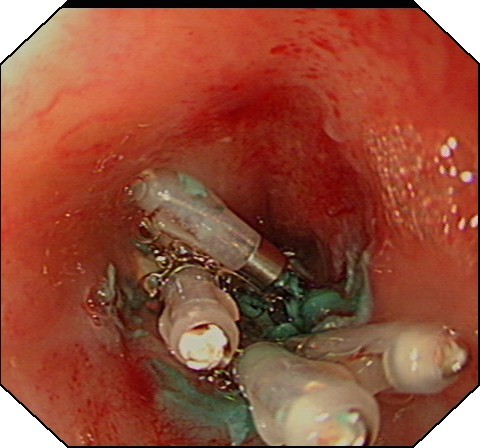

大家都知道,人体胃壁共有四层组织组成:由内到外分别为粘膜层、粘膜下层、肌层、浆膜层。胡妈妈的肿瘤就长在肌层,这是一种良性的胃肿瘤。通常,传统治疗方法一般建议外科手术治疗,开腹或开胸,有时还需要切除食管或者胃的一部分,创伤大,费用高,恢复期长。消化科吕宾教授对患者的检查资料进行仔细的研究分析,在获得患者的知情同意后,决定用国际内镜治疗的最新技术——经内镜粘膜下隧道肿瘤剥离术(STER)切除肿物。STER是通过在距肿瘤近口侧约3-5cm切开粘膜,建立粘膜下隧道(图1),逐步分离组织,显露肿瘤,再沿肿瘤包膜在内镜直视下剥离,完整剥离后取出肿瘤(图2),用金属夹关闭隧道口(图3)。

图1 建立隧道 图2 分离肿瘤